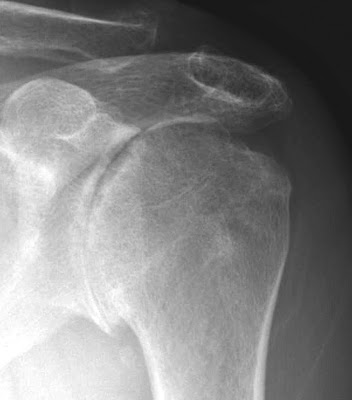

Here is an anteroposterior (AP) and an axillary view typical of shoulders with rheumatoid arthritis

The upper view, the AP shows the medial migration of the humeral head so that the lateral tuberosity is medial to the lateral acromion. There is minimal osteophytosis and periarticular osteopenia.